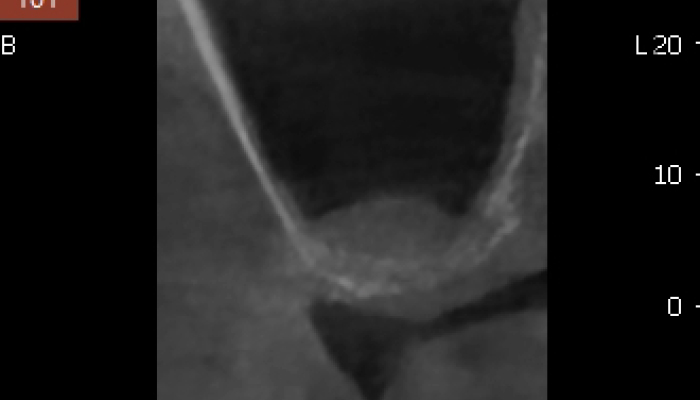

02

상악동거상술 수술사진